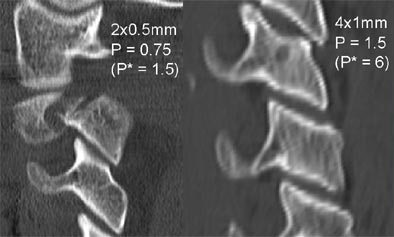

Even with minimal radiation dose, diagnostic images can be obtained by acquiring a near-isotropic secondary dataset and reconstructing with thicker slices in any plane.

| Reconstructing thicker sections (at right) reduces noise in low-dose, thin-collimation image acquisition. Images courtesy of Dr. Mathias Prokop. |